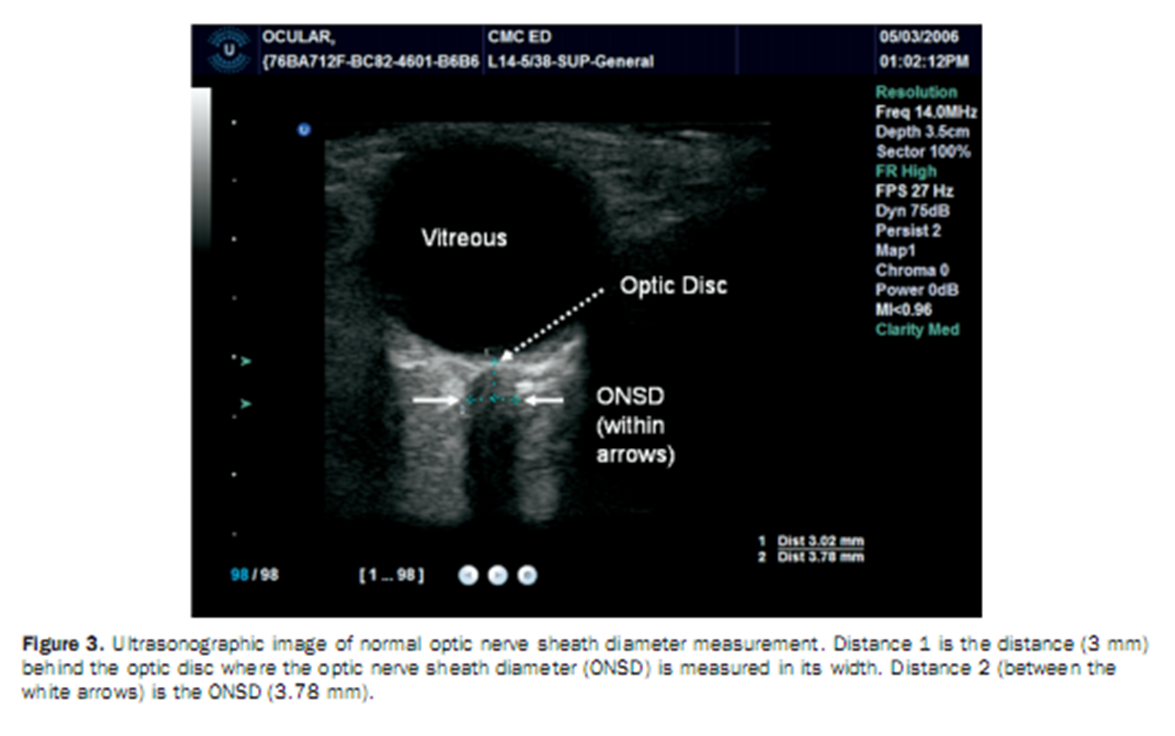

18,Siêu âm mắt